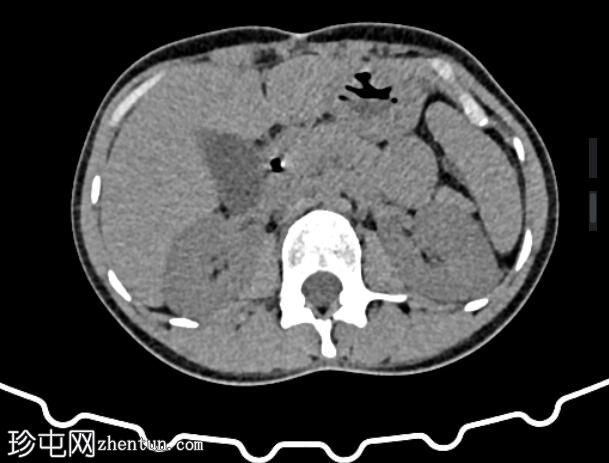

轴位增强扫描(门静脉期)

肝外胆管、肝内胆管及胆囊内可见气体。后续增强(静脉)检查中加用口服造影剂,结果显示造影剂从十二指肠反流至胆总管,最终进入胆囊。